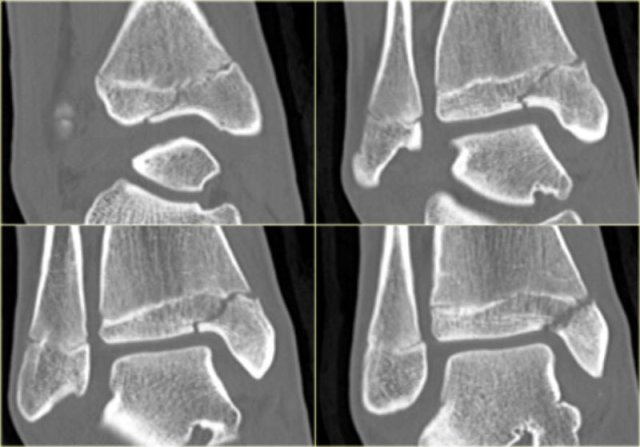

The x-ray shows a subtle Tillaux fracture, which is better appreciated on the CT-images.

Study these images carefully and remember the stages of an exorotation injury.

What is going on here?

There is a Tillaux fracture due to avulsion of the anterolateral part of the distal tibia by the anterior syndesmosis.

This can be a stage 2 of a Weber C fracture.

Stage 1 is rupture of the medial collateral ligaments and stage 3 is a fibula fracture above the level of the syndesmosis.

So now we start looking for stage 4, which is rupture or avulsion of the posterior syndesmosis.

Do you now see the tertius fracture on the axial CT-image?

This patient has an unstable ankle injury and a syndesmotic screw needs to be inserted.